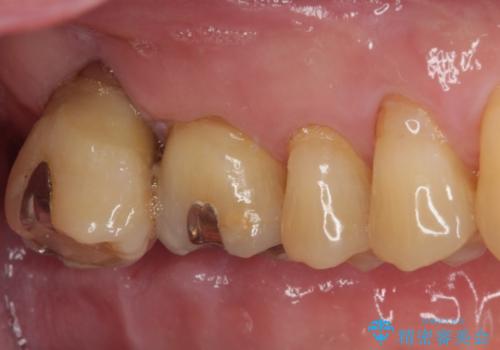

左下の奥歯は状態が非常に悪く、保存は困難と判断されたため、インプラントによる補綴治療が必要でした。

上顎左右の歯をアンカースクリューを用いた部分矯正により位置を修正し、オールセラミッククラウンにて補綴治療を行うこととしました。